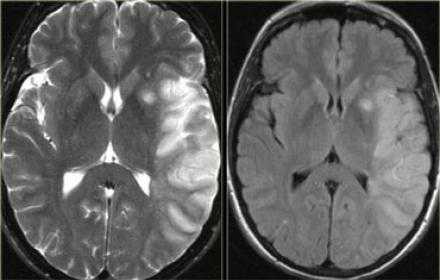

На PD/T2WI и FLAIR выглядит гиперинтенсивно. На PD/T2WI и FLAIR последовательностях возможно диагностировать до 80% инфарктов впервые 24 часа, но впервые 2-4 часа после инсульта изображение также может быть неоднозначным. На PD/T2WI и FLAIR продемонстрировано гиперинтенсивность в районе левой средней мозговой артерии. Обратите внимание на вовлечение в процесс лентиформного ядра и островковой доли. Область с гиперинтенсивным сигналом на PD/T2WI и FLAIR соответствует гиподенсивной области на КТ, что в свою очередь прямой признак гибели клеток мозга.

Диффузно-взвешенное изображение.

DWI наиболее чувствительна к инсульту. В результате цитотоксического отека возникает дисбаланс внеклеточной воды к Броуновскому движению, поэтому данные изменения выявляются отлично на DWI. В норме протоны воды диффундируют внеклеточно, поэтому теряется сигнал. Высокая интенсивность сигнала на DWI указывает на ограничение протонов воды диффундировать внеклеточно.

Представлены ДВИ инфаркт передней, задней, средней мозговой артерии.